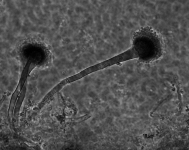

| Species Name: | Aspergillus fumigatus |

| Taxonomy: | FUNGI Ascomycota, Eurotiomycetes, Eurotiales, Aspergillaceae |

| Substrate: | skin, left ear canal; atypical showing greyish-white and blue-green sectors | Location: | CANADA Alberta, Edmonton (GEO: 53.544,-113.491) |

| Characters: | CULTURE CONDITIONS original culture slow growing and poorly sporulationg @ 25C, good growth at 37C - // MOLECULAR SYSTEMATICS Blast match 99-100% beta tubulin similarity with Aspergillus fumigatus - fide UAMH 2011 // THERMOTOLERANT - (Click for publications citing UAMH 625) |